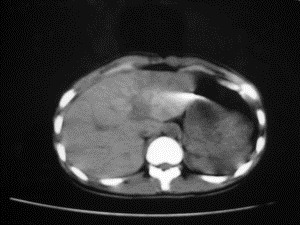

患者女,20岁,被车撞伤3小时,pe:全腹肌紧张,压痛反跳痛,以右上腹为著,肠鸣音减弱。有手术结果。![]() ![]() ![]() ![]() ![]() ![]() ![]() ![]() ![]() ![]() ![]() ![]() ![]() ![]() ![]() ![]() ![]() ![]() ![]() ![]() ![]() jiajie发言: ![]() 考虑空腔脏器穿孔。 dyqct发言:考虑:1、肝左叶外侧段断裂伤伴少量腹血。2、空腔脏器穿孔。 fangzheng发言:仅见腹腔内游离气体,提示空腔脏器穿孔。 guoke发言:胃内密度增高,肠腔内充满气体,考虑肠腔破裂出血 mmg94发言:胃后壁见一增厚软组织密度影,肝左叶前见游离气体影,左腹腔内局部肠管壁、系膜增厚。并见类圆形软组织。以上征象提示消化道管腔破裂,小肠、肠系膜挫裂伤,腹腔血肿形成。 拾荒者发言:肝实质密度不均匀,胃内见不均匀高密度影。考虑:肝挫裂伤,胃内应激性溃疡出血。 守望可可西里发言: 以下是引用jiajie在2006-6-20 15:49:00的发言:[br] [br][br]考虑空腔脏器穿孔。jiajie老师,我鼓起了很大的勇气才决定给您唱个反调儿,如果我错了,请您一定给我指出来,谢谢您了。我反复看了解剖图谱,觉得您所说的“考虑空腔脏器穿孔”上图所用箭头标明的不是游离气体。请您看以下几幅图片: ![]() ![]() ![]() ![]() ![]() ![]() ![]() ![]() 再请您看向医生老师发表的解剖图谱3幅 ![]() ![]() ![]() 这以下几幅图,我认为是肝包膜下积血。不过,说实在话,我没有发现有明显的肝挫裂伤。不对的地方请您一定指出来,再次感谢您了,jiajie 老师! ![]() ![]() ![]() ![]() 这下面几幅图片,我认为有明显的左中上腹部小肠损伤。 ![]() ![]() ![]() ![]() ![]() ![]() ![]() ![]() jiajie 老师,估计我说的是错误的,但我实在闹不明白,请您一定不要笑话我,并指出我的错误,以便于我减少工作中的失误。再次感谢您了,jiajie 老师! 至于胃内的不均匀高密度,我认为拾荒者战友说的有道理,胃内应激性溃疡出血和胃内容物混合所致。 手术结果:左肝叶(iv段)前缘长约8cm挫裂伤口,舌叶根部下< |